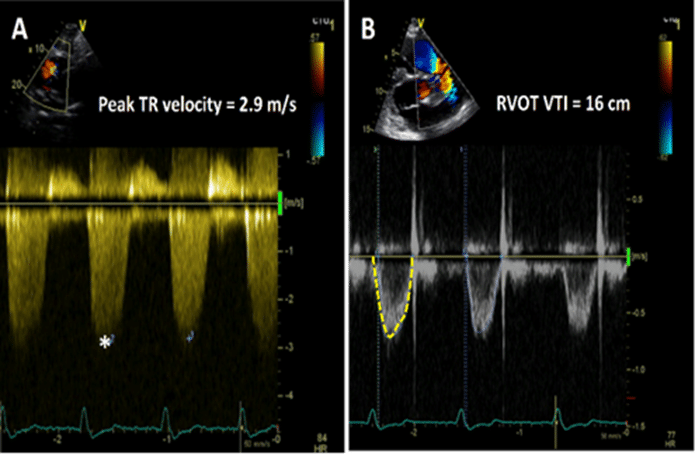

Tradingview pseudo silenPvr vascular resistance pulmonary rvot vti pw doppler measured estimated sec ratio meters tr cw peak velocity can Normal values for pwv (average according to age (1455 subjects); boxesUnderstanding vpvr.